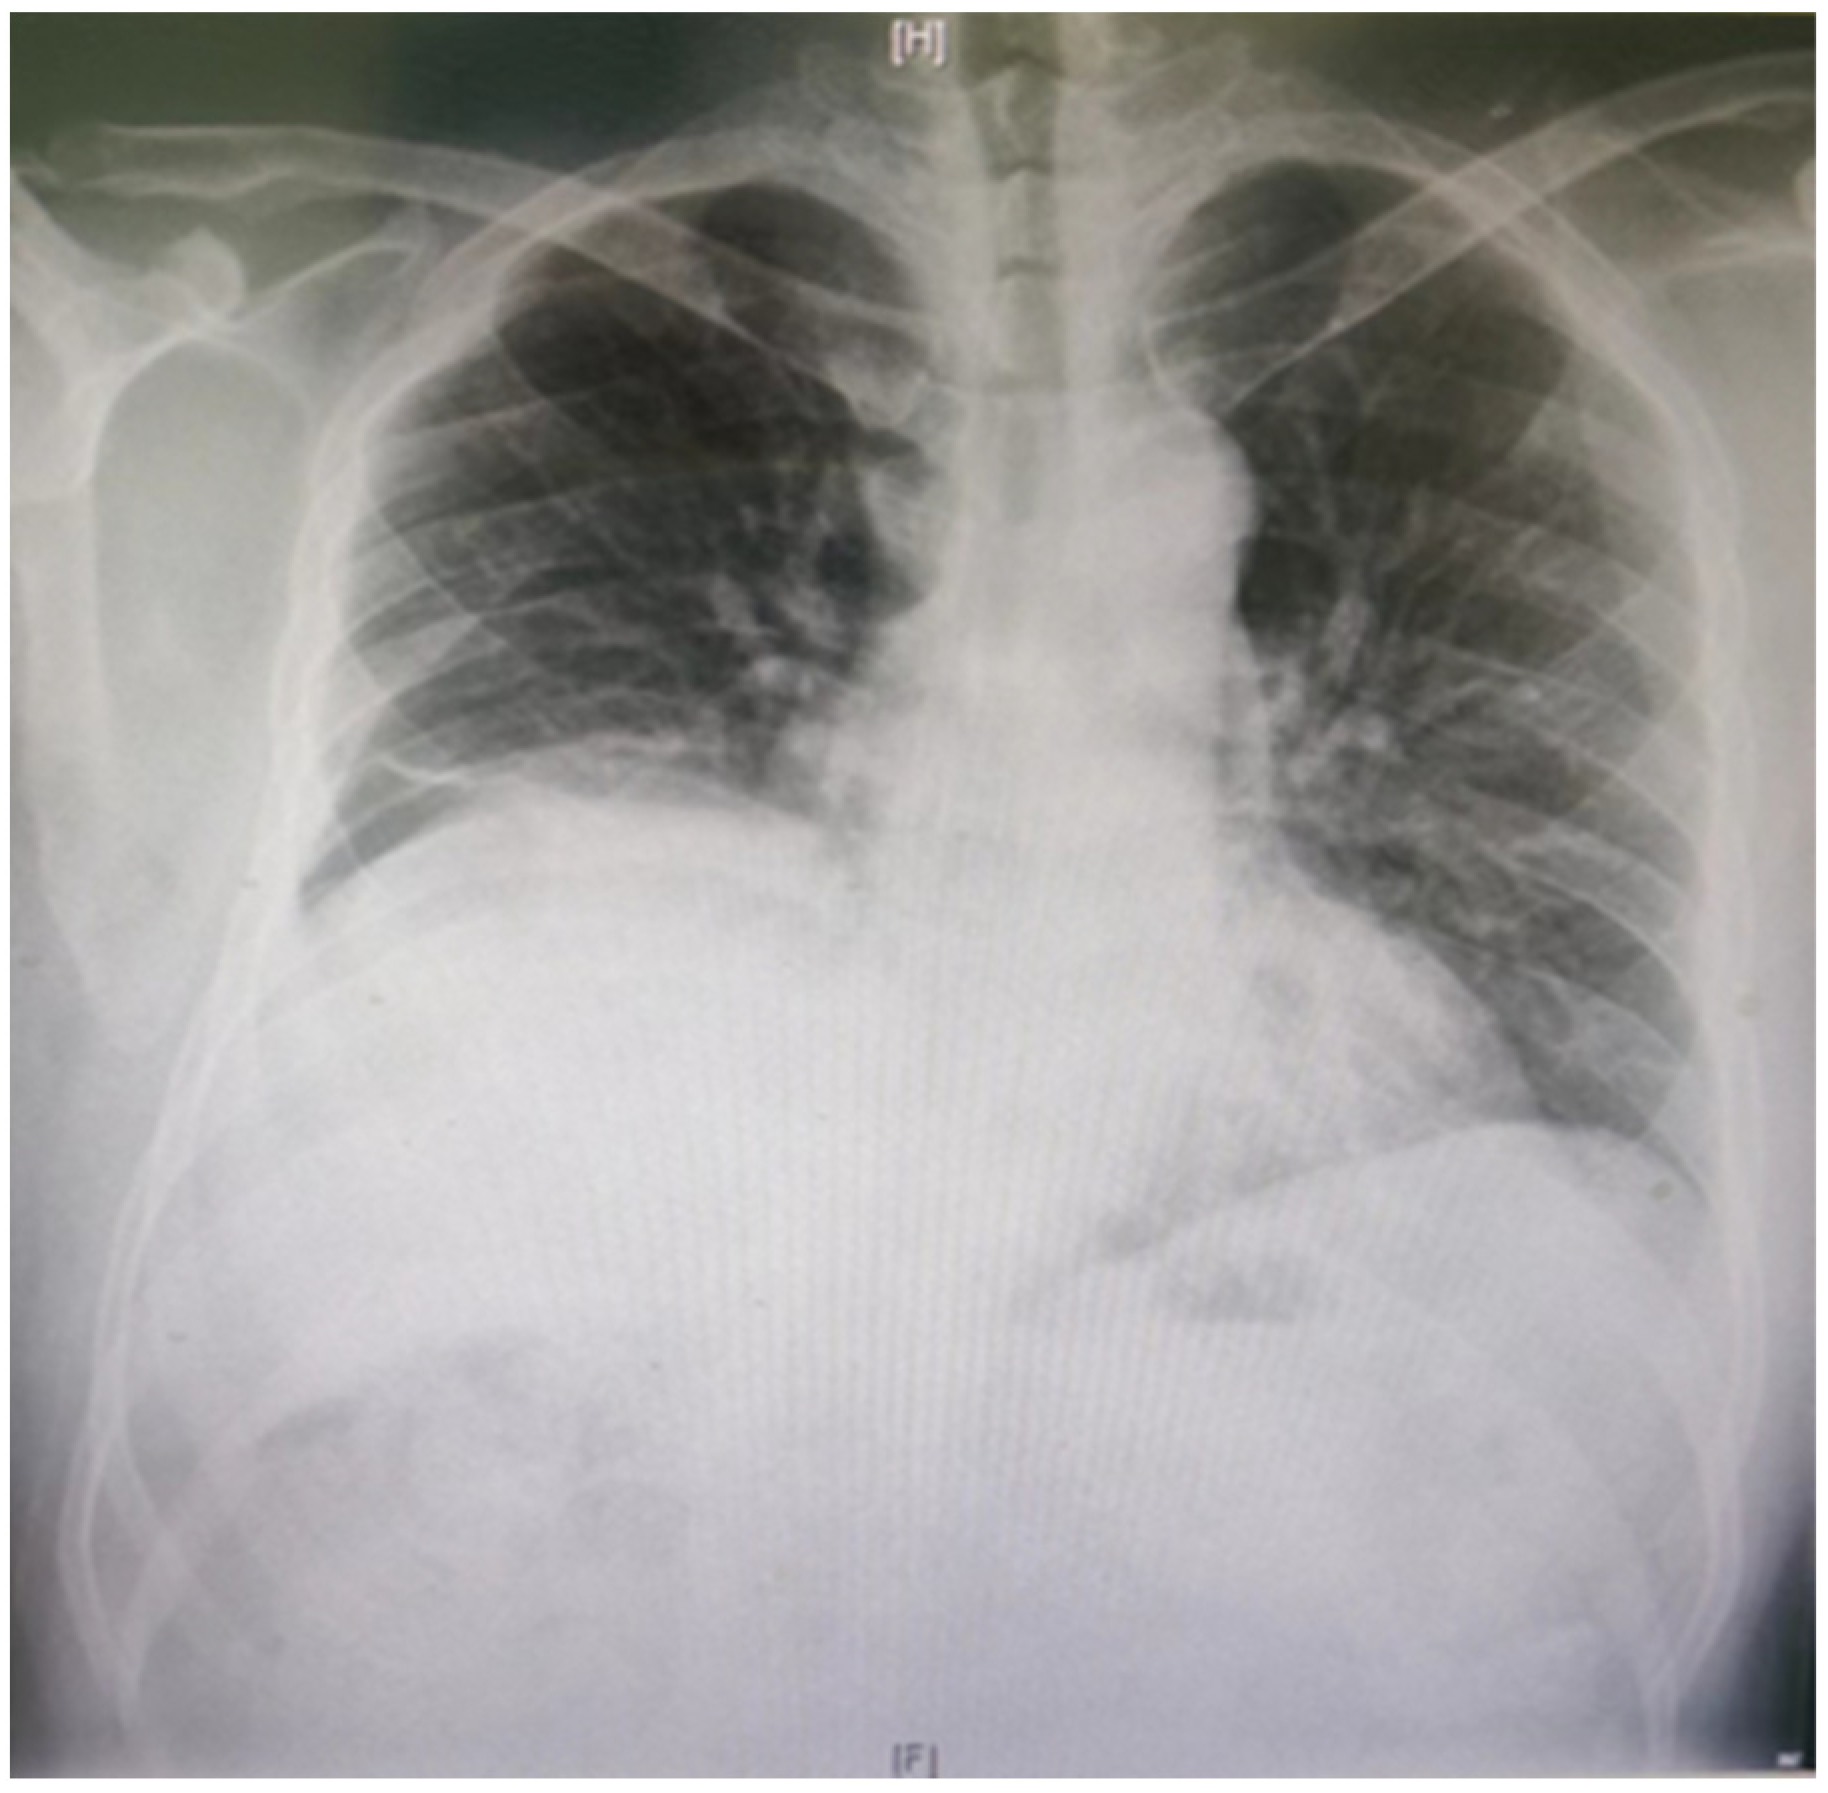

In normal individuals, the left hemidiaphragm is usually located one intercostal space lower than the right hemidiaphragm. The negative pressure inside the chest will push the hemidiaphragm into the chest cavity if it is weak. Therefore, a paralyzed hemidiaphragm is always at a higher level (Figure 2). Although an elevated hemidiaphragm, as shown on a chest radiograph, is often a sign contributing to the diagnosis of unilateral paralysis, a similar radiographic appearance could also be observed in cases of diaphragmatic eventration, subpulmonic effusion, lobar atelectasis, or subphrenic abscess [36]. The chest X-ray diagnosis of DD has a high sensitivity and low specificity of 90% and 44%, respectively [37].

Figure 2. The chest radiograph shows the pathological elevation of the right hemidiaphragm.